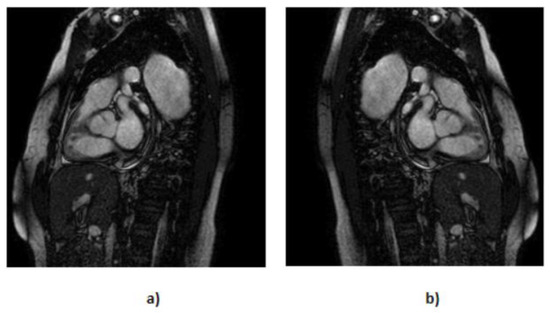

- We executed translation along the x-axis (Figure 5) while meticulously ensuring that the aortic valve remained within the frame; with this, we created 202 more MRIs out of the original dataset.